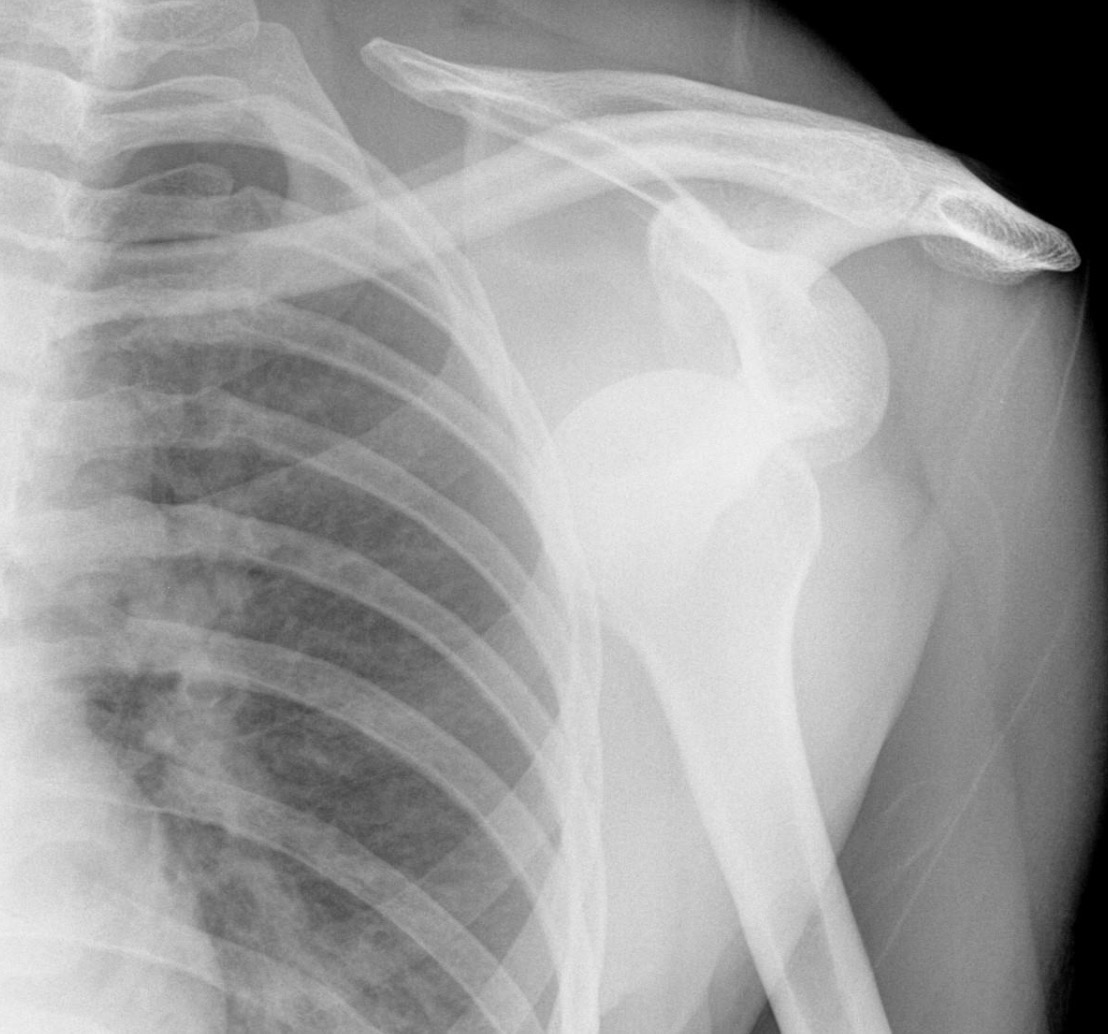

Shoulder dislocation (Anterior) ⭐

Most common dislocation

Mostly moves anteriorly and inferiorly